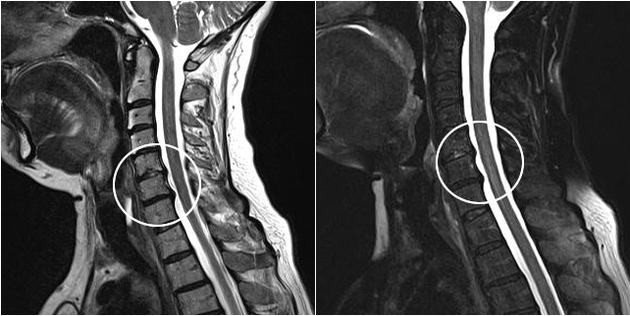

I moderni metodi diagnostici includono la risonanza magnetica e la TC, che consentono di esaminare con maggiore precisione i processi di distruzione della cartilagine e del tessuto osseo. Inoltre, utilizzando questa tecnica è conveniente diagnosticare ernie e altri difetti dei tessuti molli vicino alla fonte della malattia.